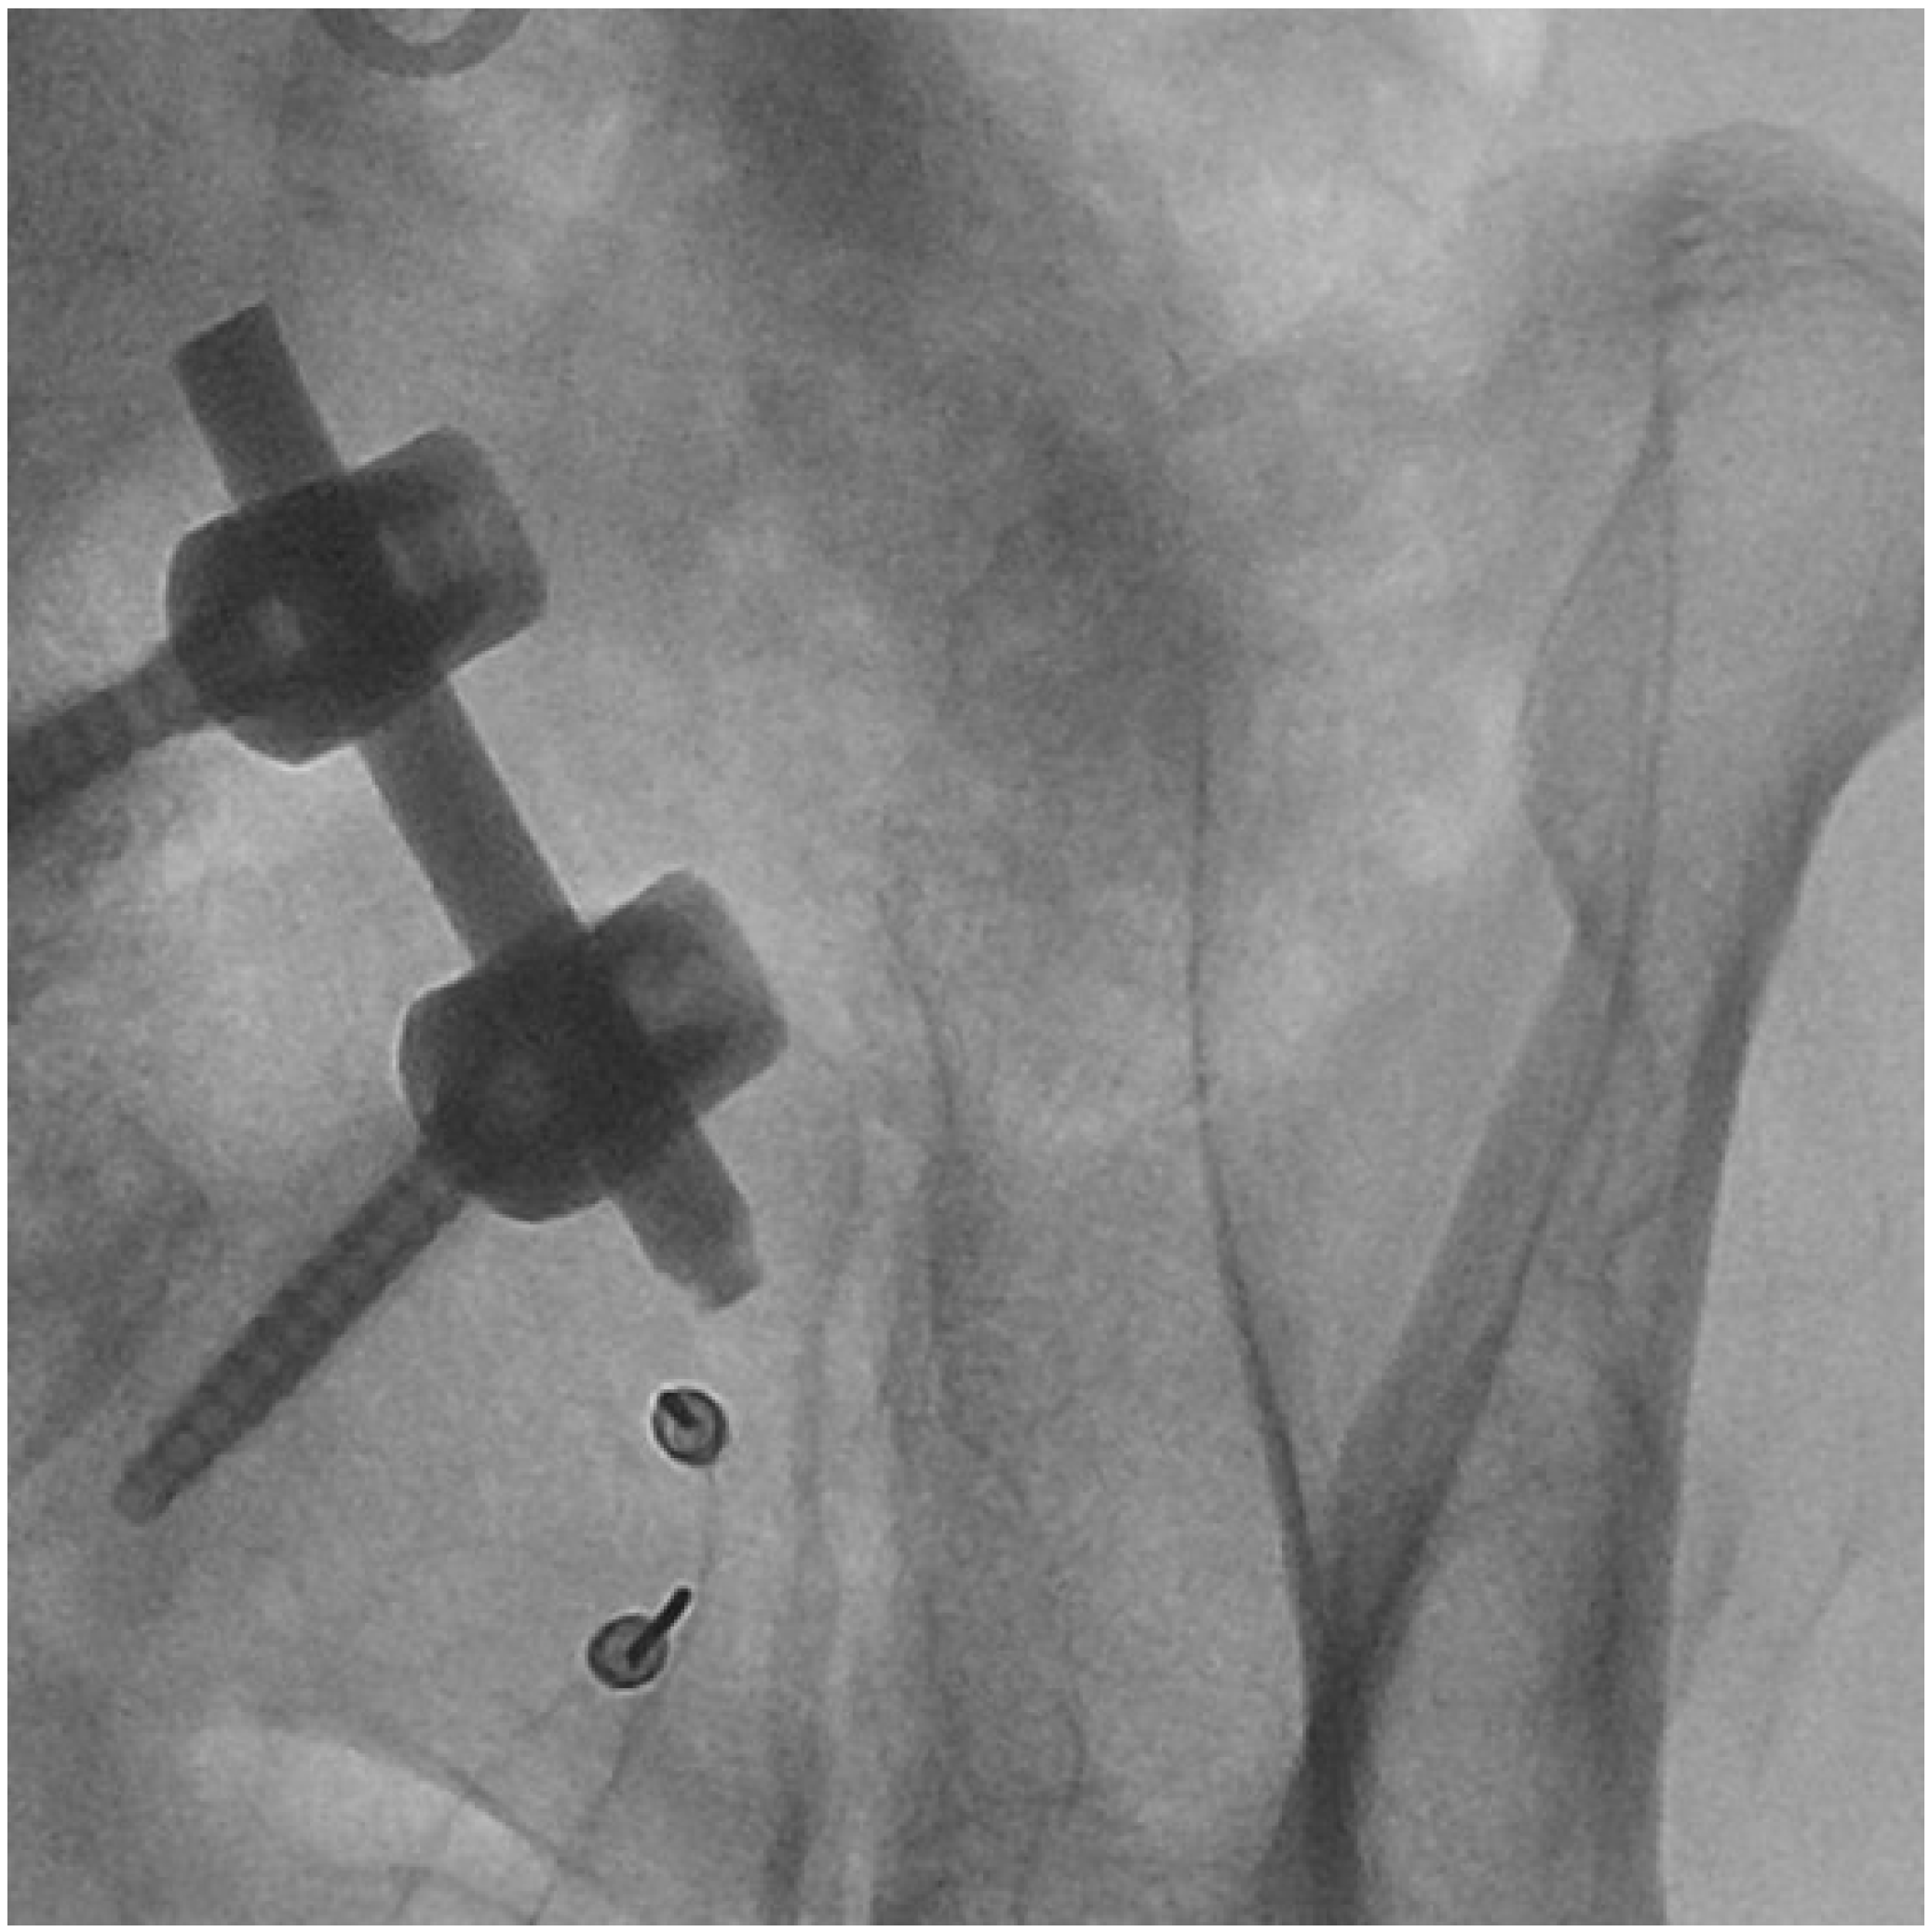

2. Methods